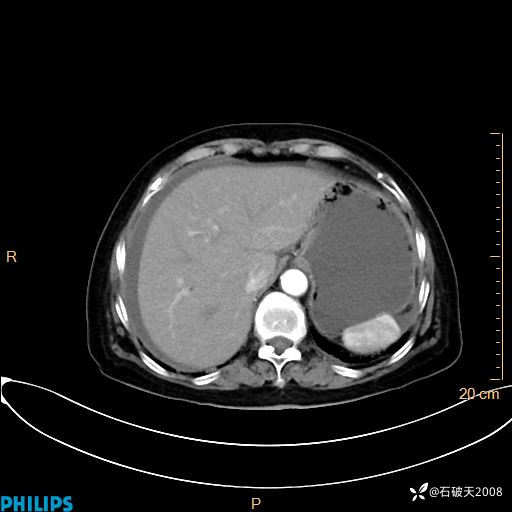

动脉期